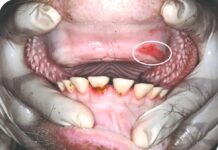

Kod 5704 krava ( 60 %), na papcima su utvrđene bolesne promjene. Najučestalija dijagnoza je laminitis 44,61 %, slijede dermatitis digitalis (mortelaro) 10,75 % te čir tabana 10,35 %. S obzirom da se kod većine krava radilo o težem stupnju promjena procijenjeno je da ekonomski gubitak radi smanjene mliječnosti i plodnosti te ranijih izlučenja na tim farmama, zbog bolesti papaka, iznosi oko 2600 kuna po kravi godišnje.